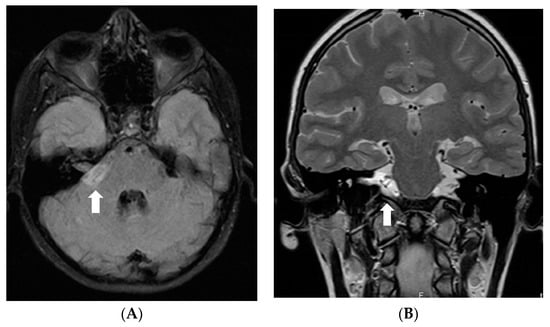

In July 2011, a 16-year-old girl was admitted to Hospital of Lithuanian University of Health Sciences Kauno klinikos due to severe headache, vomiting, and vertigo lasting 2 days. She had a half-year history of similar paroxysms usually beginning with numbness in hands or in one side of face or leg. Neurological examination revealed right-sided peripheral facial paresis, horizontal nystagmus, painful exit points of branches of the right trigeminal nerve, slight deviation of the uvula to the right, right-sided hemiparesis, and cerebellar ataxia. Moreover, papilledema was observed. Brainstem evoked potentials response audiometry showed no clear waves on the right side although hearing was normal. Magnetic resonance imaging (MRI) of the head demonstrated a hyperintense mass on T2W/FLAIR images with heterogenous enhancement in the right cerebellopontine angle cistern and internal auditory canal (Figure 1). All figures in this manuscript are non-published and original.

Figure 1.

Initial MRI of the brain at our clinic (July 2011): (A) Axial T2W/FLAIR and (B) coronal T2W images demonstrate a hyperintense mass in the right cerebellopontine angle cistern and internal auditory canal. (C) Axial and (D) coronal T1W postcontrast images show heterogenous enhancement in the referred area.